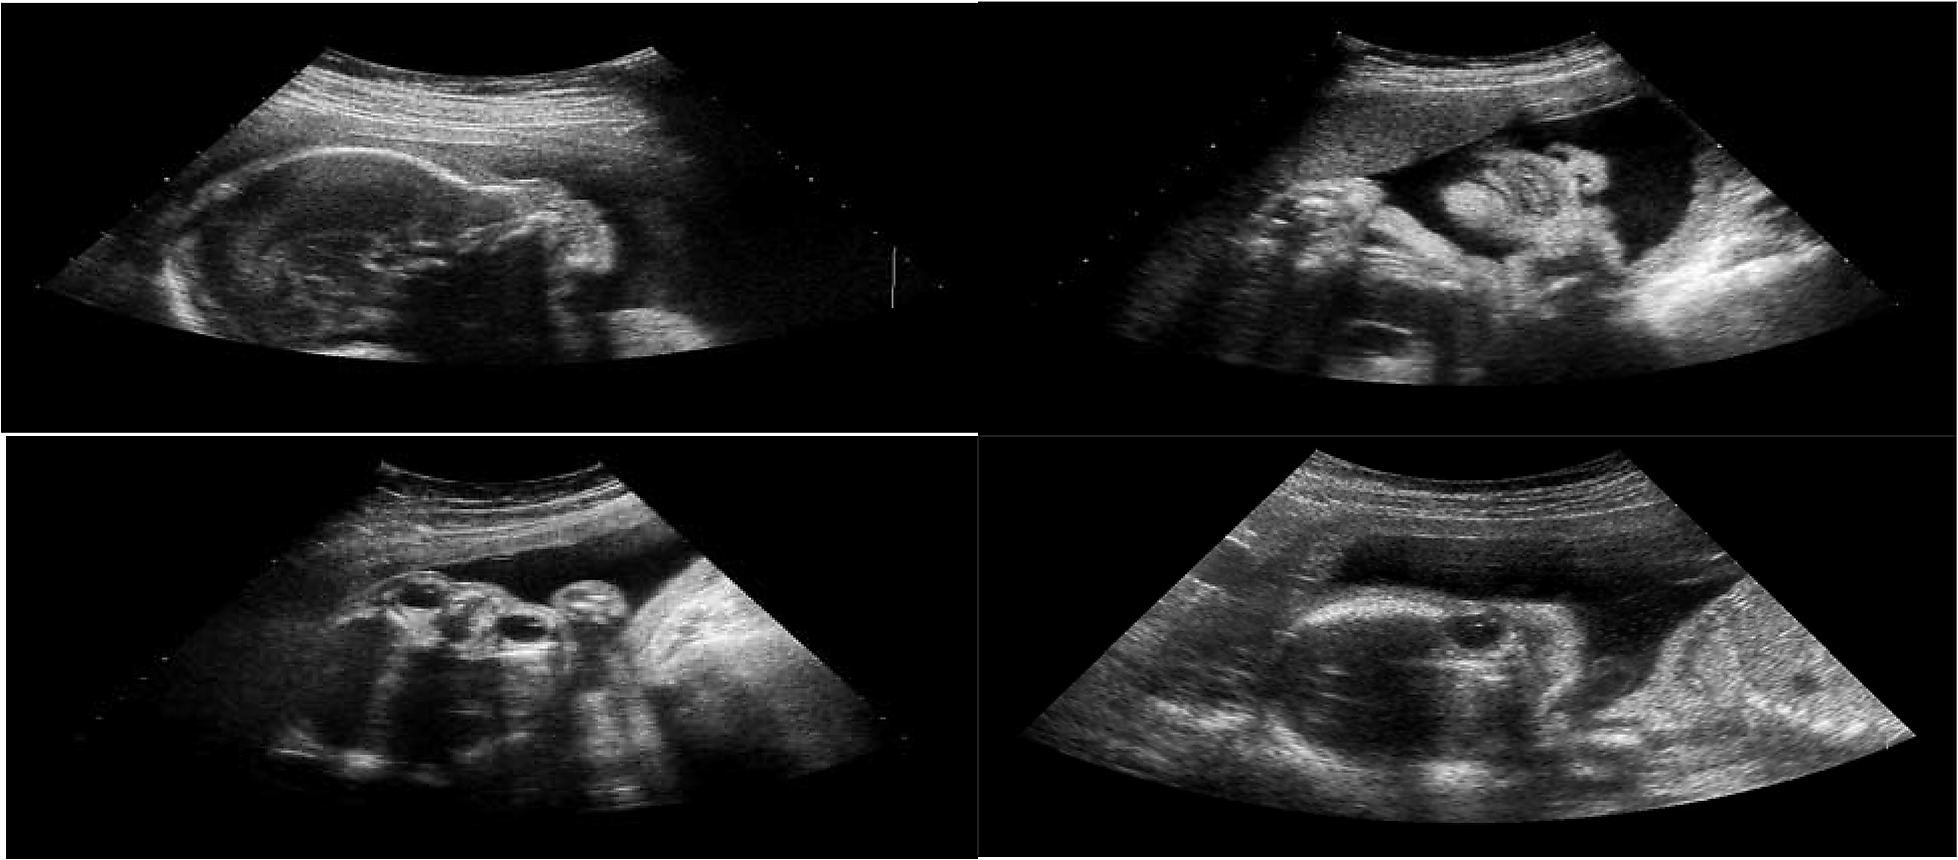

Hình ảnh siêu âm thai